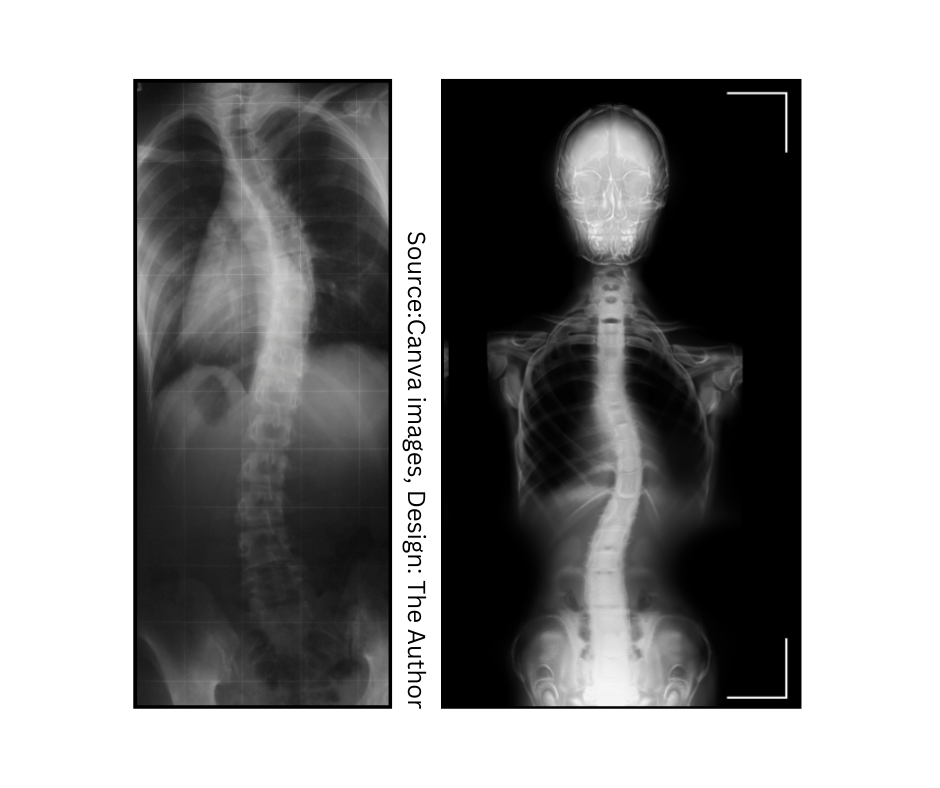

I explore scoliosis, chronic pain, disability, and inclusion through lived experience and neuroscience.

Musculoskeletal health issues, such as back pain, shoulder pain, hip pain, and knee pain, or in my case, scoliosis are among the most common physical health issues affecting individuals of all ages. Their impact goes far beyond physical discomfort. These conditions influence daily activities, work productivity, and overall quality of life - turning what begins as a minor issue into a major limitation, even for individuals previously considered healthy (without disability).

Holding a Diploma in higher nursing, having 1st class practice experience, living with severe scoliosis, and managing challenging health conditions consequences included: tiredness, fibromyalgia, fatigue, chronic muscoskeletal pain, I consider myself an expert in managing pain. I am still being optimistic type of Soul, and when you meet me, you wouldn't probably guess what's going on with me, unless I tell you. I am friendly, but professional.